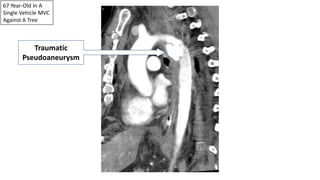

67 Year-Old In A

Single Vehicle MVC

Against A Tree

Traumatic

Pseudoaneurysm